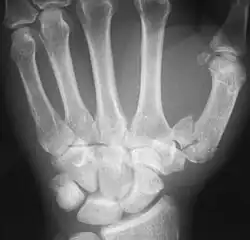

The first metacarpal bone or the metacarpal bone of the thumb is the first bone proximal to the thumb. It is connected to the trapezium of the carpus at the first carpometacarpal joint and to the proximal thumb phalanx at the first metacarpophalangeal joint.

The first metacarpal bone is short and thick with a shaft thicker and broader than those of the other metacarpal bones. Its narrow shaft connects its widened base and rounded head; the former consisting of a thick cortical bone surrounding the open medullary canal; the latter two consisting of cancellous bone surrounded by a thin cortical shell. [1]

Fractures

Fractures to metacarpal bones account for 30-40% of all hand fractures, of which 25% occur in the first metacarpal (second to fractures to the fifth metacarpal bone). 80% of fractures to the first metacarpal occur at its base. [6]

Common fractures to the thumb metacarpal include Bennett's fracture and Rolando's fracture

Fracture of the first metacarpal (Rolando's fracture). -